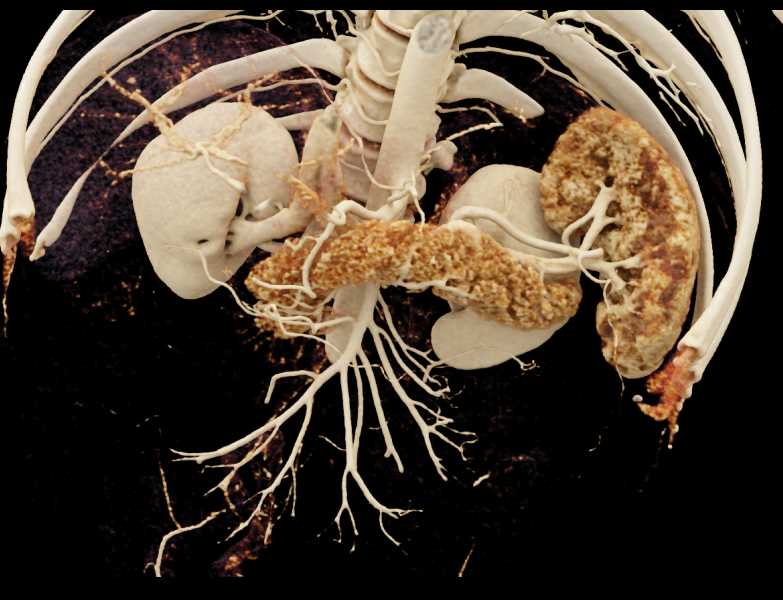

Subtle Neuroendocrine Tumor Body of Pancreas